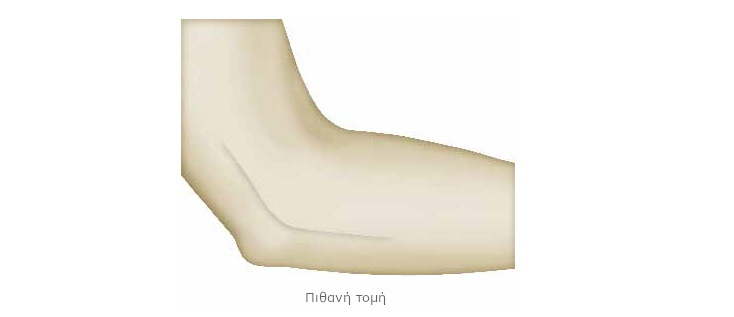

Ο χειρουργός πραγματοποιεί τομή περίπου 10 εκατοστών, στο ύψος της αύλακας του ωλενίου νεύρου.